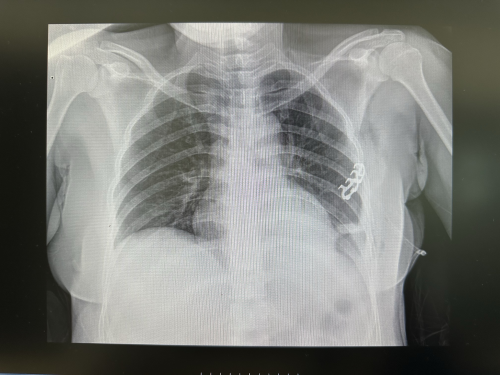

吴女士(化名)因车祸致头面部、胸部等多处受伤,胸部CT提示:左侧多发肋骨骨折,有明确手术指征。

肋骨骨折是较常见的胸部创伤,关于肋骨骨折的检查,不论是广大患者还是临床医师首先想到的当然是X线。近年来,随着CT技术和超声技术的日趋成熟,肋骨超声已逐步成为临床确诊隐匿性肋骨骨折新兴的、有效的手段。尤其对于肋软骨骨折的患者,由于X线和CT不显影,MRI价格更贵、预约时间长,肋骨超声检查几乎是首选的方便、有效、快捷的影像学检查手段。